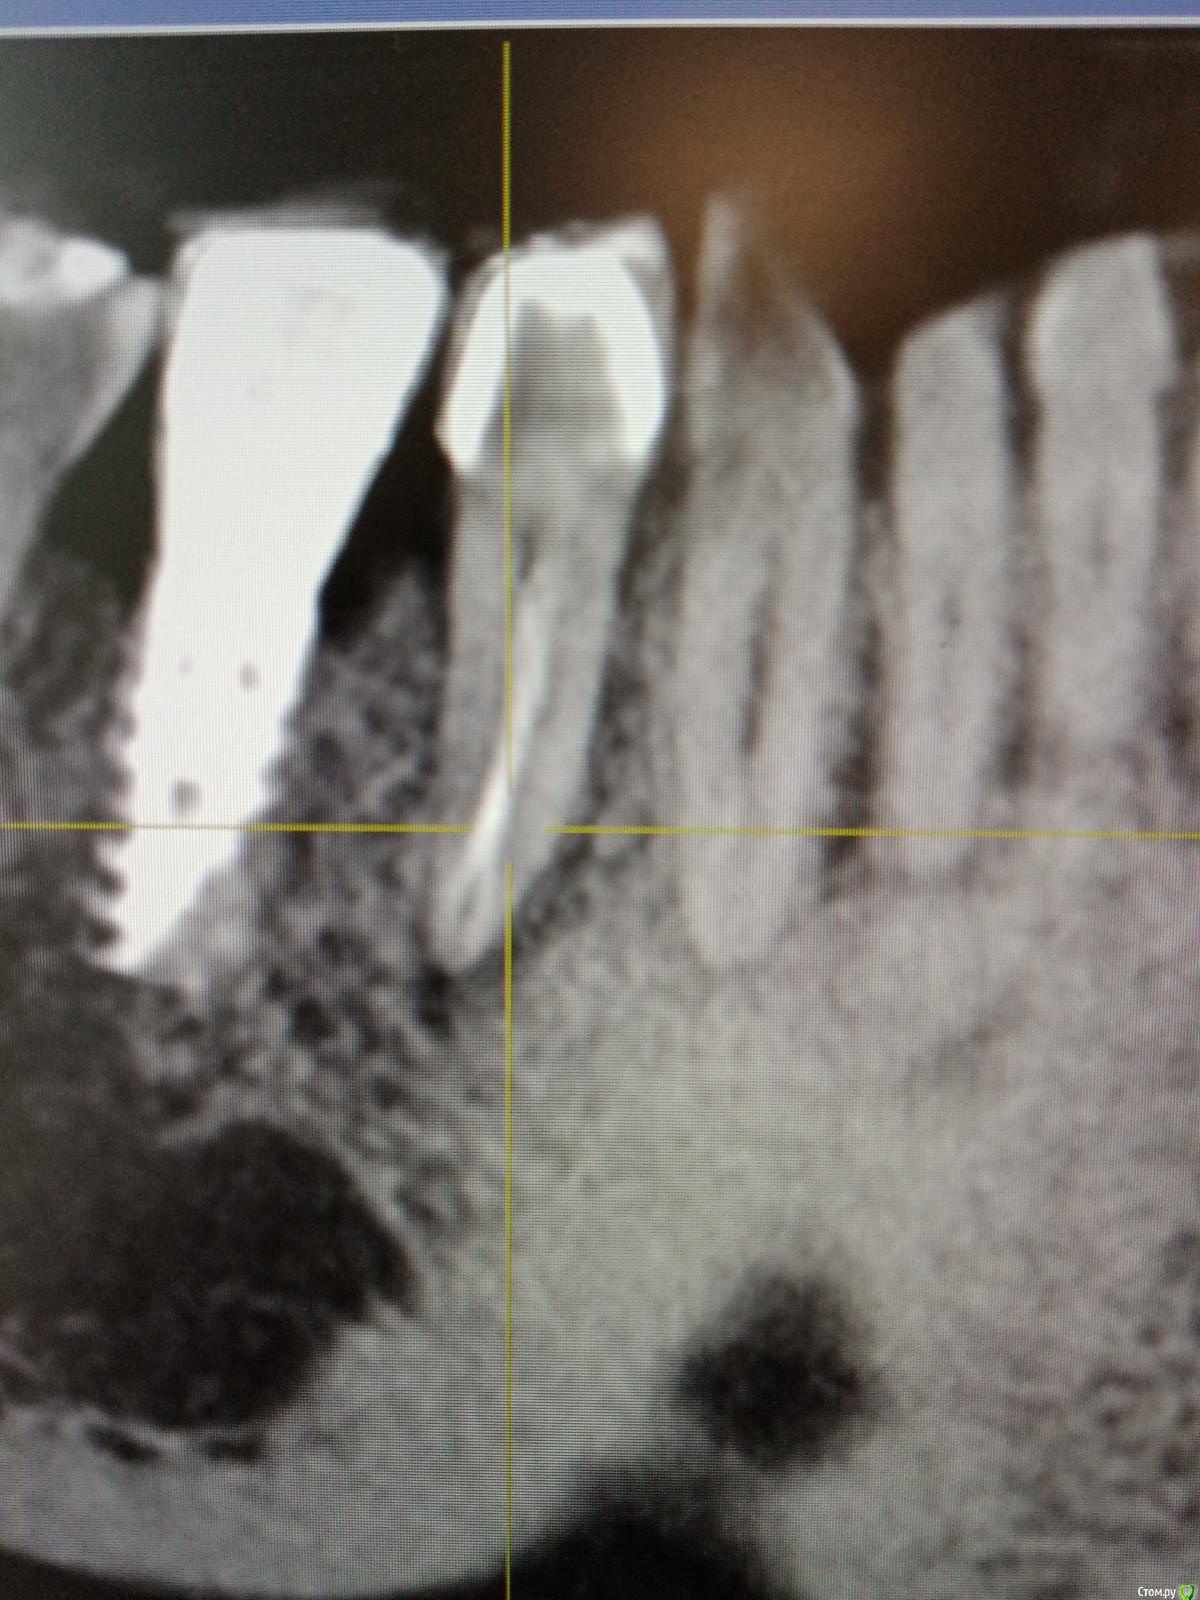

Raimar Опубликовано 30 июня, 2020 Поделиться Опубликовано 30 июня, 2020 (изменено) Зуб 4.5, ранее лечен, (эндо), пациентка пришла ко мне на перелечивание с острой болью, основную гуттаперча удалил,далее файл упирается, нужно ли пытаться распломбировать маленькие канальцы? Изменено 30 июня, 2020 пользователем Raimar Ссылка на комментарий

vse32 Опубликовано 1 июля, 2020 Поделиться Опубликовано 1 июля, 2020 Не, кт уже вижу. По-хорошему прямо надо каналы пройти. Ссылка на комментарий